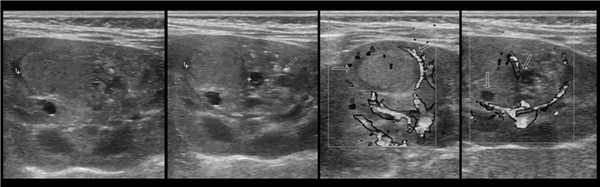

В марте 2002 г. в связи с эпизодом лейкоцитурии лечился у нефролога; при контрольном УЗИ впервые диагностированы изменения в мочевом пузыре и паравезикально слева. При повторном УЗИ выявлено (рис. 1а): правая почка увеличена в размерах (длина 12,7см; толщина паренхимы 1,6 см); чашечно-лоханочная система не расширена. Левая почка отсутствует. Стенки мочевого пузыря не изменены; в просвете слева определяется округлое образование 3,5 x 4,6 x 5,0 см с неоднородным содержимым (объем около 40 мл). Заключение: аплазия левой почки; уретероцеле слева.

а) Эхограмма.

Рисунок. У новорожденного на УЗИ почек определяется гидронефроз (1) и расширенный мочеточник (2) справа. В мочевом пузыре двустороннее уретероцеле (3). При исследовании левой почки структурных изменений не выявлено.

Рисунок. На УЗИ определяется удвоенная чашечно-лоханочная система, расширена лоханка верхнего сегмента (1) и мочеточник на всем протяжение (2, 3), в мочевом пузыре уретроцеле (4). Полное или неполное удвоение чашечно-лоханочной системы возможно увидеть с помощью КТ-урографии.

Рисунок. Дистальный отдел мочеточника расширен, в мочевом пузыре анэхогенное образование с тонким и ровным контуром — уретероцеле.

Рисунок. Двустороннее уретероцеле на УЗИ: в режиме ЦДК из верхушек уретероцеле определяется выброс мочи.

Рисунок. На УЗИ в уретероцеле определяется гиперэхогенная структура с акустической тенью — камень. Уретероцеле может являться одним из факторов, способствующих камнеообразованию.